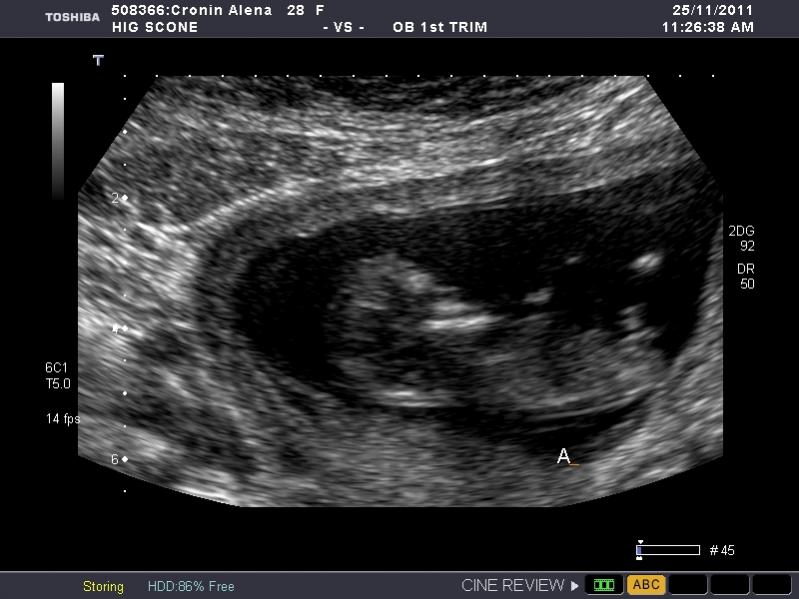

I have heaps of photos and I don't know what I am looking at so if the photo I post isn't showing anything let me know and I will try another. I am nervous as anything because I so so want a girl, but of course would still be happy with a boy. The ultrasound tech wouldn't guess.

So what is your guess.

Attachment 845Attachment 846